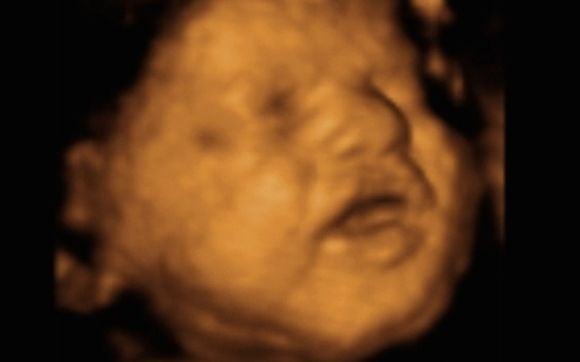

Trice Imaging Inc On Twitter How Do You Tricefy This Adorable